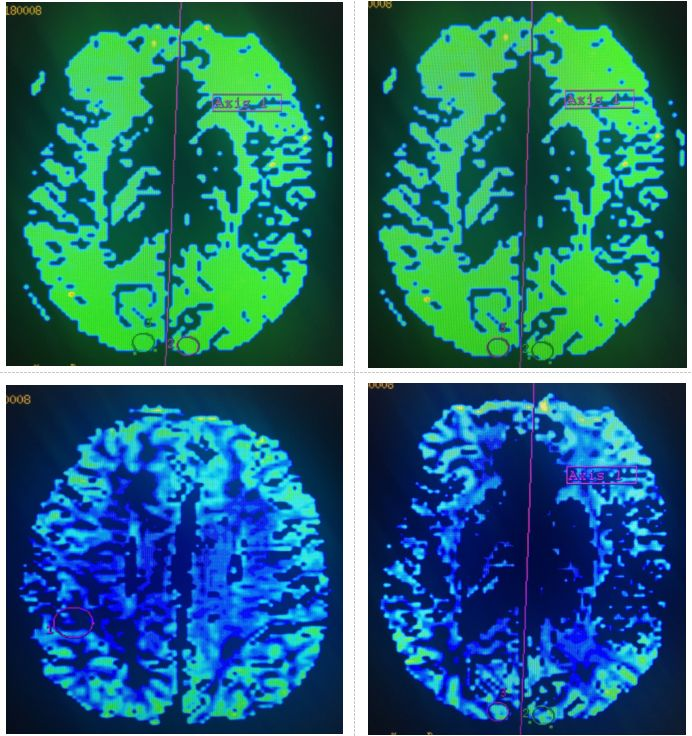

图2. 核磁灌注成像示左侧枕叶、左侧半卵圆区脑血容量(CBV)值升高,平均通过时间(MTT)延长,脑血流量(CBF)升高,达峰时间(TTP)延长

考虑患者存在大血管狭窄,核磁灌注提示左侧半球低灌注,再发卒中的风险极大,具备介入治疗指征,但存在术后高灌注的风险。向患者家属详细交代病情及介入治疗的相关风险后,家属同意进行介入诊治。于2017-12-20拟局麻下行脑血管造影+左颈内动脉起始部及岩骨段支架成形术。